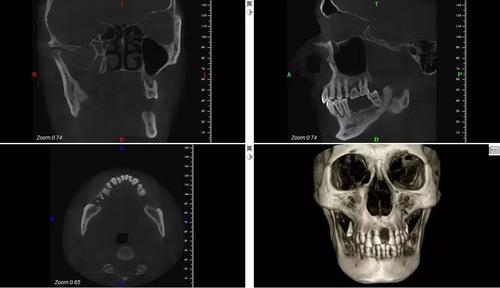

口腔ct也被称为影像学,它的检查原理与人体口腔中的口腔锤痕差不多。口腔内测试效果有几种,一种是含有x射线的X射线,一种是含有x射线的射线。